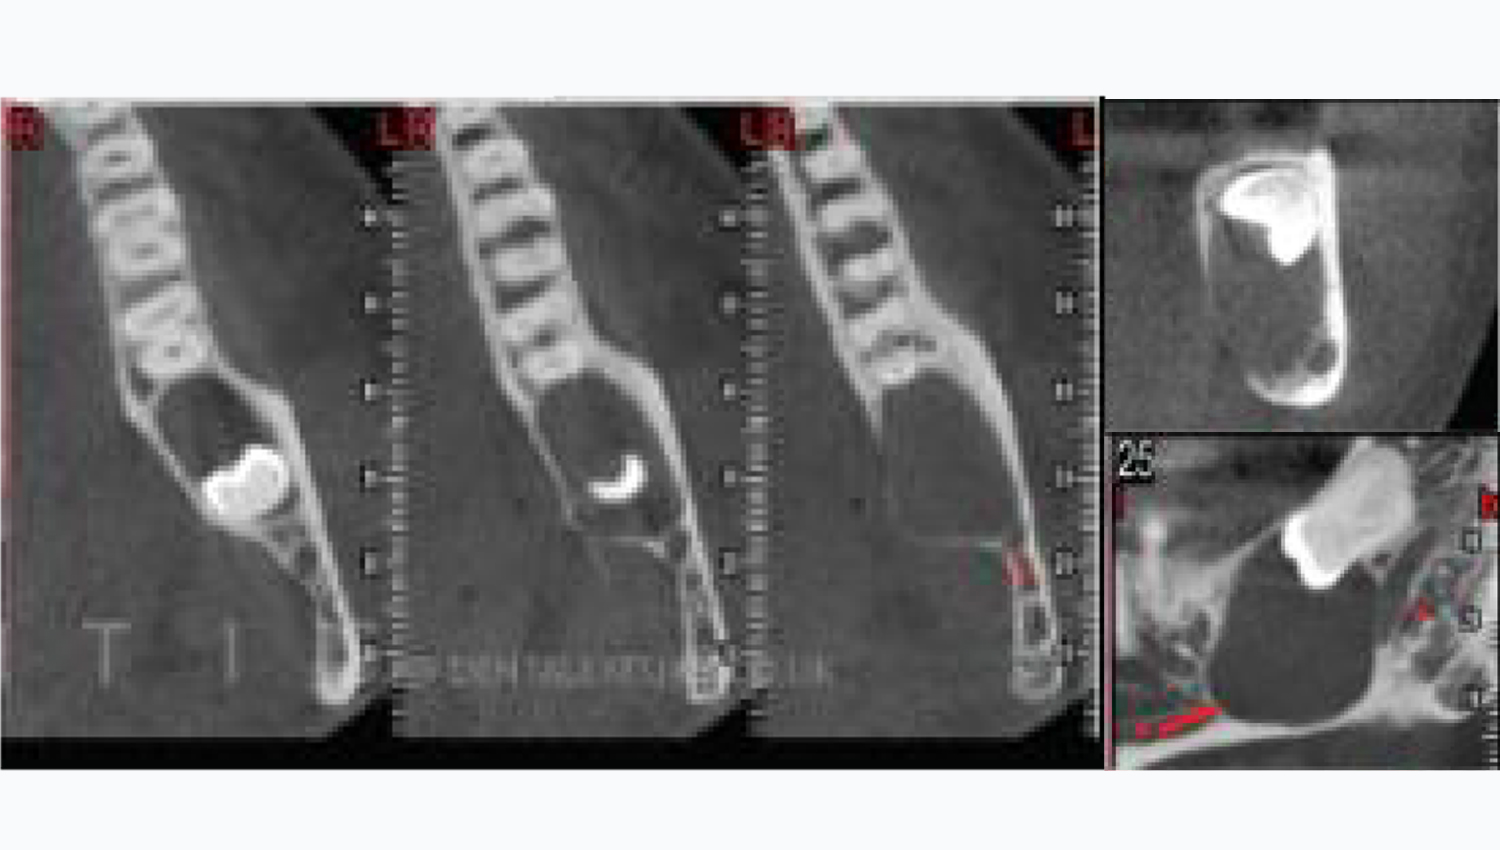

2. Initial periapical x-ray.